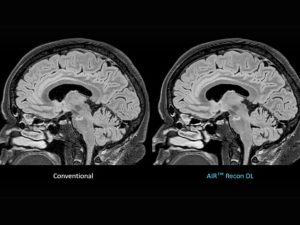

GE HealthCare has introduced three advanced deep learning solutions as part of its Effortless Recon DL portfolio. The objective of these AI-powered technologies, which include Sonic DL for 3D, Clarify DL, and TrueFidelity DL, is to address critical challenges in radiology, including the enhancement of diagnostic confidence, the reduction of scan durations, and the enhancement of image quality. GE HealthCare's dedication to utilizing artificial intelligence to improve patient outcomes is evident in the solutions that are specifically designed to assist in the early diagnosis and treatment of complex conditions such as cancer, cardiovascular disease, and neurological disorders. Sonic DL for 3D, for example, reduces MRI scan times by up to 86% while delivering high-resolution imaging for brain, spine, and body scans, while Clarify DL enhances bone SPECT imaging with superior resolution.

The Effortless Recon DL portfolio offers a range of deep learning-powered tools across multiple imaging modalities, including CT, PET/CT, and MRI. Each solution is designed to streamline workflows, enhance diagnostic precision, and address the burnout challenges faced by radiologists. These advancements reflect GE HealthCare’s broader mission to revolutionize clinical imaging by integrating cutting-edge AI technologies. By optimizing image clarity and reducing procedural complexity, GE HealthCare aims to empower clinicians worldwide to deliver timely, accurate, and cost-effective care to their patients.